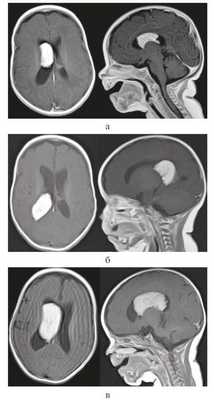

Девочка, 4 мес жизни. Ребенок от 2-й беременности, протекавшей без осложнений, роды в срок, родоразрешение посредством кесарева сечения. Первый ребенок из двойни. С рождения девочка была более сонлива, чем второй ребенок, что настораживало мать. Это явилось причиной проведения ультразвукового исследования (УЗИ) головного мозга в возрасте ребенка 3 нед. Обнаружено объемное образование в полости черепа, при МРТ подтвержден диагноз опухоли правого бокового желудочка (рис. 1, а).

Рисунок 1. МРТ с контрастным усилением в аксиальной (слева) и сагиттальной (справа) проекции: ПСС тела и переднего рога правого бокового желудочка. а — возраст ребенка 1 мес; б — возраст ребенка 2 мес: миграция ПСС в задний рог правого бокового желудочка; в — возраст ребенка 3 мес: миграция ПСС в тело и передний рог правого бокового желудочка.

Отсутствие клинической симптоматики, малый возраст ребенка послужили поводом для динамического наблюдения.

Контрольная МРТ головного мозга через 1 мес выявила миграцию опухоли в задний рог правого бокового желудочка, размер опухоли немного увеличился (см. рис. 1, б).

На контрольной МР-томограмме головного мозга выявлено значительное увеличение размеров опухоли и ее миграция в передний рог и тело бокового желудочка (см. рис. 1, в).